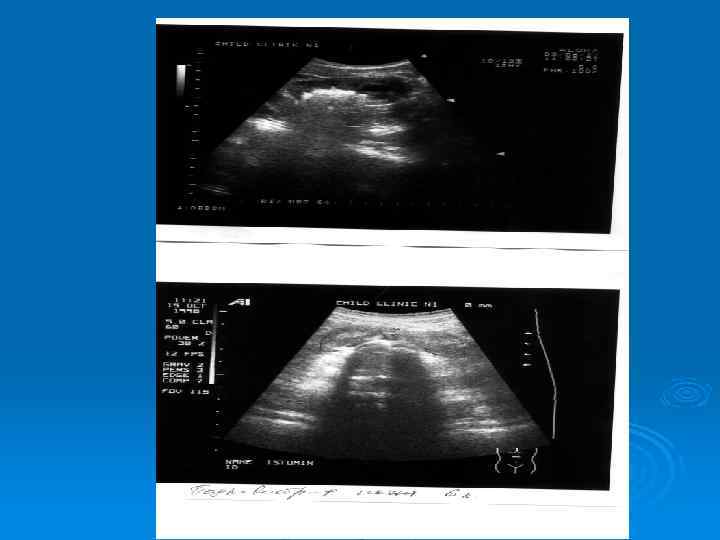

Утолщение стенки лоханки при остром пиелонефрите

Абсцесс верхнего полюса почки у ребенка, 11 лет